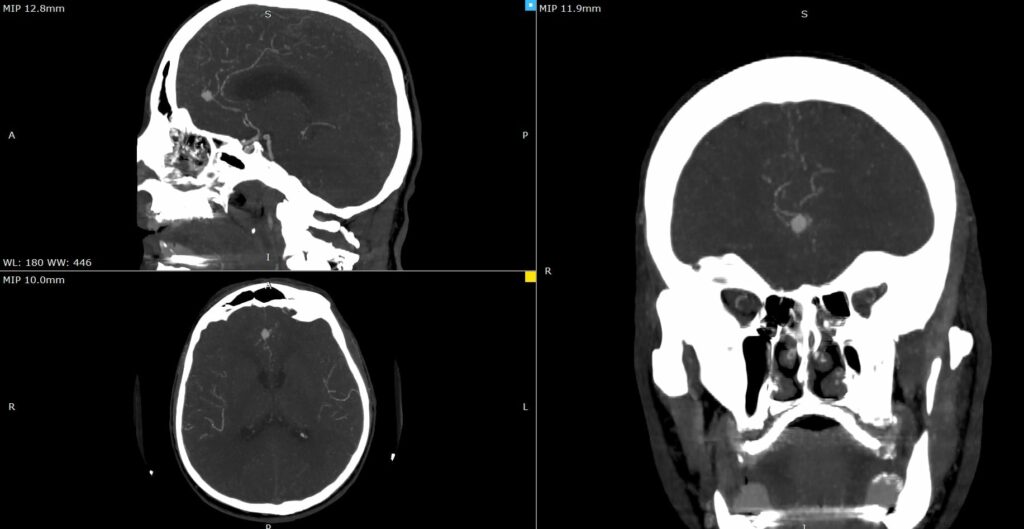

Оваа иновативна метода претставува напредна техника која овозможува визуелизација на крвниот проток во реално време за време на операцијата.

„Со примена на контрастно средство, хирурзите можат прецизно да ја проценат проодноста на крвните садови и да го потврдат целосното исклучување на аневризмата, што е клучно за успешен исход“, појаснува д-р Благој Шунтов, специјалист по неврохирургија и раководител на тимот.

Операцијата помина без компликации, а пациентот се опоравува без потешкотии. Примената на оваа напредна техника претставува значаен напредок во третманот на неврохируршки пациенти и потврдува посветеност на ЈЗУ УК за неврохирургија во примена на најновите медицински технологии.